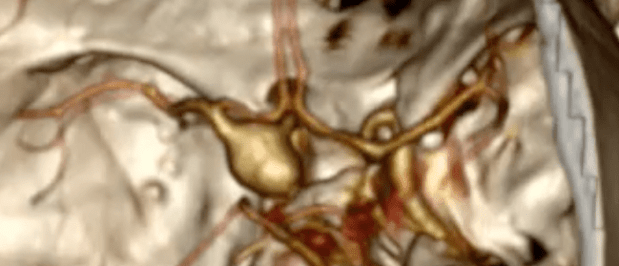

Aneurisma cerebral

Aneurisma cerebral é uma dilatação das artérias do cérebro. Artérias são os vasos sanguíneos que levam o sangue ao cérebro, em contraste aos vasos que levam o sangue do cérebro de volta ao coração, que são chamados de veia. Este sangue é bombeado pelo coração, sob pressão, e levam nutrientes para o cérebro funcionar normalmente. Continue lendo “Aneurisma cerebral”